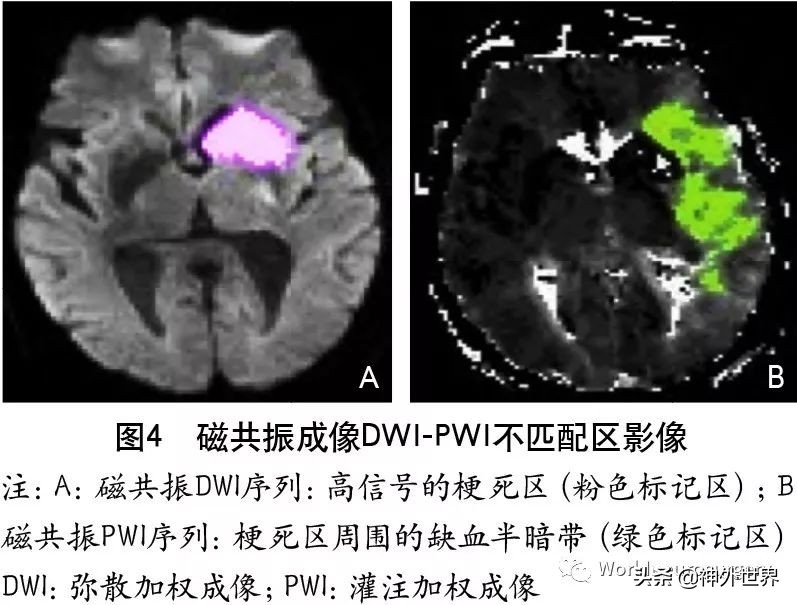

5.2.3 磁共振成像DWI-PWI不匹配区

MRI PWI常采用动态磁敏感对比增强技术,通过对比剂团注追踪技术进行动态增强扫描,依靠对比剂磁化率改变引起信号变化的原理成像。经处理后可得出相应灌注成像的参数如CBF、CBV、MTT及TTP等。研究表明,CBF下降和MTT延长是组织缺血的相对敏感指标,但存在过分估计最终梗死体积的可能性;TTP图像上脑灰质、白质之间无明显区别,可以清楚显示病变的范围和边界。虽然目前识别缺血半暗带的方法有多种,但MRI DWI与PWI不匹配区是急诊过程中判断缺血半暗带较切合实际的方法(图4)。一项回顾性研究认为,PWI的病灶面积是DWI病灶面积的2.6倍时早期再灌注的治疗效果最好。